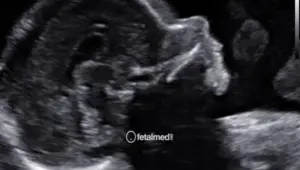

• Translucência nucal (TN) — medida do espaço na nuca do feto, marcador principal para rastreio de Síndrome de Down e outras cromossomopatias

• Osso nasal — sua presença ou ausência é um marcador adicional importante

• Ducto venoso — avaliação do fluxo sanguíneo, que pode indicar alterações cardíacas